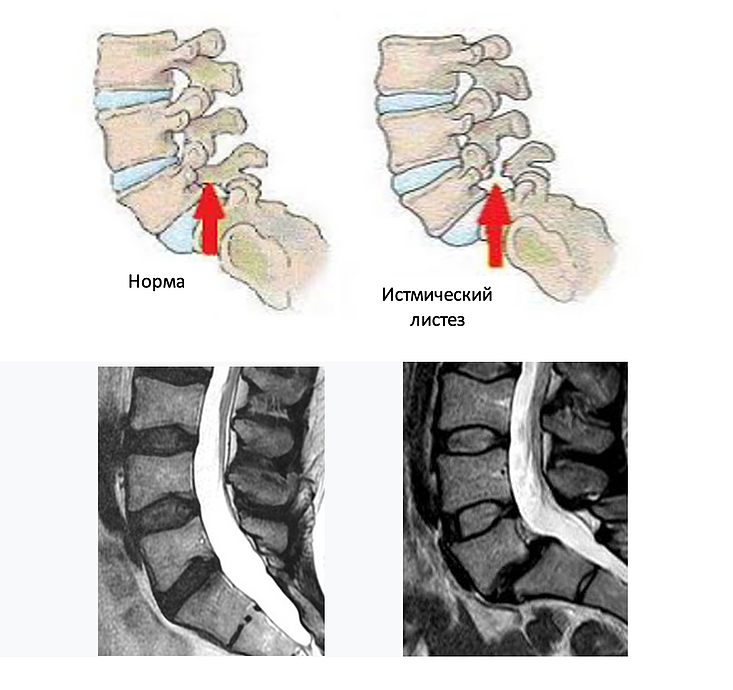

7. МРТ - уже позволило увидеть реальную проблему. Как оказалось, у меня истмический листез.

На картинке можно сразу понять, в чем проблема.